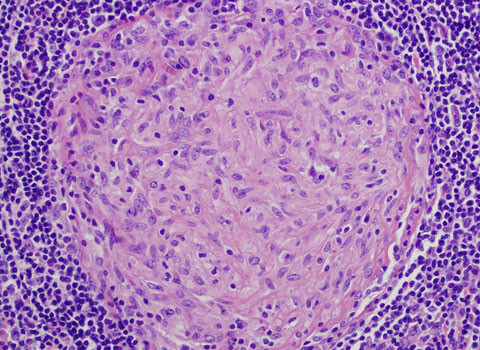

Các cơ quan tự hủy. Sau khi bị đông cứng, cơ thể bắt đầu phân rã. Enzyme trong tuyến tụy làm cơ các cơ quan trong cơ thể bắt đầu tự hủy. Vi khuẩn sẽ cùng kết hợp với những enzyme này, biến cơ thể từ vùng bụng trở nên có màu xanh lá cây. Khi các vi khuẩn này tấn công chúng ta, nó giải phóng putrescine và cadaverine, tạo ra mùi kinh khủng mà chúng ta vẫn ngửi thấy.